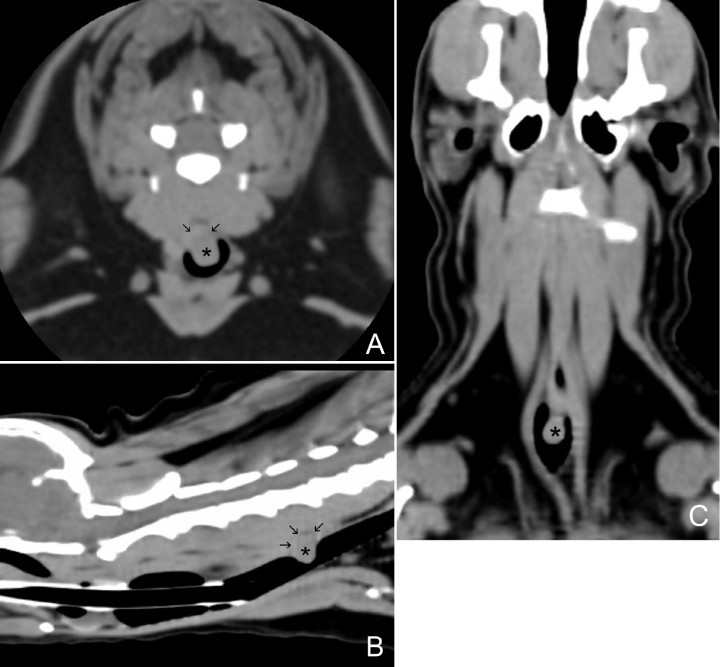

Posteriormente, se realizó una Tomografía Computarizada (TC) donde se evidenció que la masa visualizada previamente no solo protruía hacia el interior de la luz traqueal, ya que presentaba una pequeña extensión dorsalmente (Fig. 6). La masa era ligeramente hipoatenuada (50 UH) en relación con la musculatura paraespinal (62 UH) y sus dimensiones aproximadas eran de 0,9 cm (altura) x 0,75 cm (longitud) x 0,5 cm (anchura), no observándose evidencia de metástasis o invasión a estructuras adyacentes, y percibiendo los linfonodos y el parénquima pulmonar sin alteraciones evidentes.

<p>Imágenes de tomografía computarizada (TC) en plano transversal (<strong>A</strong>) y reconstrucciones en planos sagital (<strong>B</strong>) y dorsal (<strong>C</strong>) en ventana de tejidos blandos del cuello del paciente, en las que se puede visualizar una estructura redondeada de atenuación tejido blando (50 UH), de base ancha (asterisco) que protruye hacia el exterior e interior de la luz de la tráquea desde la pared dorsal, a nivel del cuerpo vertebral de C5 (flechas).</p>

Imágenes de tomografía computarizada (TC) en plano transversal (A) y reconstrucciones en planos sagital (B) y dorsal (C) en ventana de tejidos blandos del cuello del paciente, en las que se puede visualizar una estructura redondeada de atenuación tejido blando (50 UH), de base ancha (asterisco) que protruye hacia el exterior e interior de la luz de la tráquea desde la pared dorsal, a nivel del cuerpo vertebral de C5 (flechas).

Una masa traqueal puede ser visualizada y valorada mediante radiografía simple de tórax y fluoroscopia, debido a que la presencia de aire que la rodea permite delimitar sus márgenes. Sin embargo, la TC y la traqueoscopia son las herramientas que más información aportan sobre el tamaño y las características morfológicas de la masa, aunque el diagnóstico definitivo solamente es posible mediante el estudio histopatológico.[ Ramírez GA, Altimira J, Vilafranca M. Cartilaginous tumors of the larynx and trachea in the dog: Literature review and 10 additional cases (1995-2014). Vet Pathol 2015; 52:1019-1026. [PubMed] ] La traqueoscopia ofrece la posibilidad de evaluar el grado de obstrucción de la luz traqueal y el aspecto de la masa, y permite la toma de una muestra para estudio citológico o histopatológico.[ Honings J, Gaissert H, Van der Heijden H, et al. Clinical aspects and treatment of primary tracheal malignancies. Acta Otolaryngol 2010; 130: 730-772. [PubMed] ] En este caso, no se tomó muestra vía endoscópica de la masa por el riesgo de edema/sangrado y complicaciones subsiguientes. Por otro lado, la TC es de gran ayuda para planificar la cirugía al aportar información sobre el grado de infiltración, la extensión de la masa y la posible presencia de metástasis locales y distantes.[ Honings J, Gaissert H, Van der Heijden H, et al. Clinical aspects and treatment of primary tracheal malignancies. Acta Otolaryngol 2010; 130: 730-772. [PubMed] ] En nuestro caso, las imágenes tomográficas evidenciaron un mayor volumen de la masa al poder observar un crecimiento de la misma extra e intraluminal, y constató la ausencia de metástasis tanto a nivel pulmonar como en estructuras adyacentes. Consideramos una limitación del estudio el no haber realizado un estudio postcontraste que hubiera mostrado el patrón de realce de la masa y quizás nos hubiera proporcionado un diagnóstico presuntivo más certero/aproximado, ya que una masa tipo pólipo presenta captación de contraste de manera periférica o “en anillo”, una neoplasia tipo carcinoma suele mostrar un realce heterogéneo y los linfomas, por lo general, tienen captación homogénea de contraste.[ Tanaka T, Akiyoshi H, Mie K, et al. Contrast-enhanced computed tomography may be helpful for characterizing and staging canine gastric tumors. Vet Radiol Ultrasound 2019; 60: 7-18. [PubMed] ]